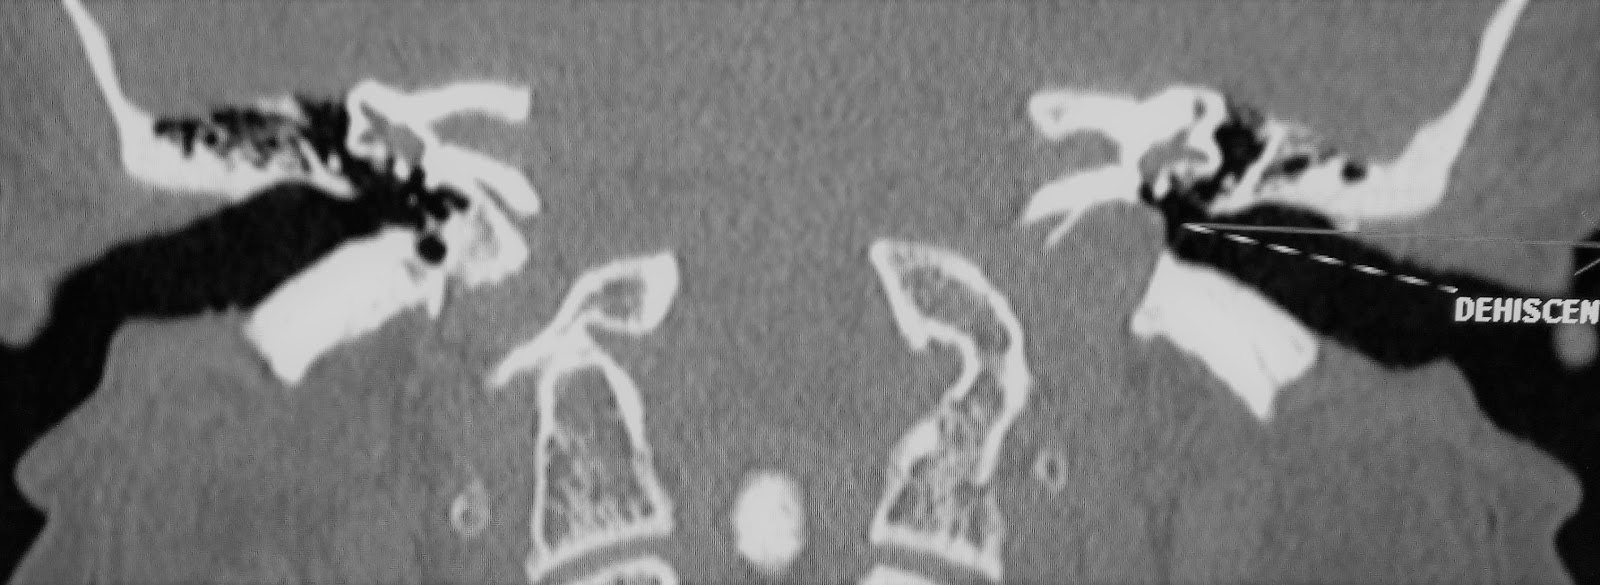

Dehiscent jugular bulb CT Sumer's Radiology Blog

What Is Jugular Bulb . Eric beek and frank pameijer. Radiology department of the university medical centre of utrecht, the netherlands. Web the jugular bulb is the connection between the sigmoid sinus and the internal jugular vein. Web jugular bulb is the expanded upper end of the jugular vein situated in. Web temporal bone pathology. In this case, the sigmoid plate which is normally present between a high riding jugular bulb and middle ear cavity, is absent which defines this as a focal dihiscence. Web the jugular bulb diverticulum is a much rarer anomaly than high riding jugular bulb (stern and goldeberg, 1980). Web a high riding jugular bulb indicates the dome (roof) of the jugular bulb extends more superiorly in the petrous.

What Is Jugular Bulb In this case, the sigmoid plate which is normally present between a high riding jugular bulb and middle ear cavity, is absent which defines this as a focal dihiscence. Web a high riding jugular bulb indicates the dome (roof) of the jugular bulb extends more superiorly in the petrous. Web the jugular bulb diverticulum is a much rarer anomaly than high riding jugular bulb (stern and goldeberg, 1980). Eric beek and frank pameijer. Web the jugular bulb is the connection between the sigmoid sinus and the internal jugular vein. In this case, the sigmoid plate which is normally present between a high riding jugular bulb and middle ear cavity, is absent which defines this as a focal dihiscence. Web jugular bulb is the expanded upper end of the jugular vein situated in. Radiology department of the university medical centre of utrecht, the netherlands. Web temporal bone pathology.